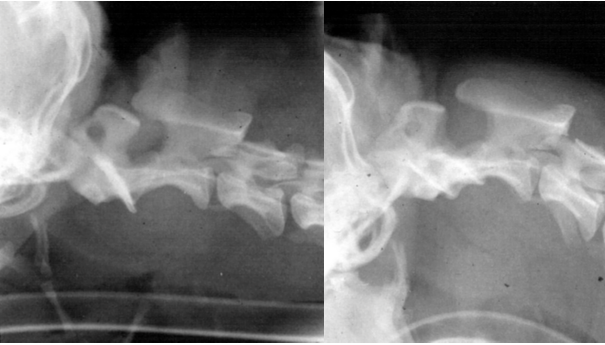

• what is the diagnosis?

atlantoaxial subluxation